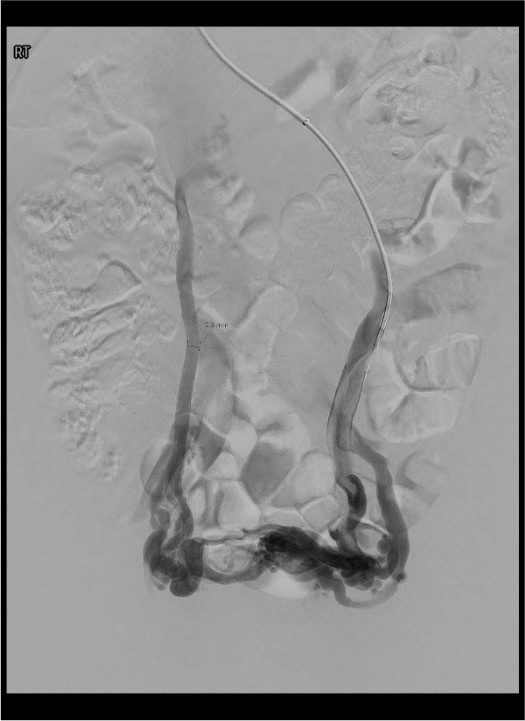

Step 2 — Access and Venographic Assessment

- Access: right internal jugular vein (preferred — favorable angle for left renal/ovarian vein) or right common femoral vein; 5–6 Fr sheath.

- Left renal venogram: 5 Fr cobra or reverse-curve catheter; identify ovarian vein ostium; selective left renal venogram with Valsalva. Evaluate for nutcracker anatomy (renal vein diameter ratio, pressure gradient >3 mmHg).

- Left ovarian venogram: advance into gonadal vein; Valsalva to confirm reflux and map pelvic collaterals and escape points.

- Right ovarian venogram: direct IVC catheterization; right gonadal vein origin smaller and more oblique.

- Bilateral internal iliac venograms: with Valsalva; identify refluxing tributaries (pudendal, obturator, inferior gluteal) and escape points. These are the main driver of recurrence if untreated.

Iliac Vein Stenting (Secondary Obstruction)

When PeVD is caused by May-Thurner syndrome or nutcracker syndrome, treat the obstruction first before addressing gonadal vein reflux:[2][3][15]

- A single-center series (n=45 women, 38% MTS alone, 53% MTS + nutcracker) treated with bilateral iliac vein balloon angioplasty ± stenting ± ovarian vein embolization showed significant reductions in pain scores and analgesic use.[16]

- Iliac vein stenting for MTS without acute DVT (n=34) achieved 68% clinical success; female sex correlated with better outcomes.[17]